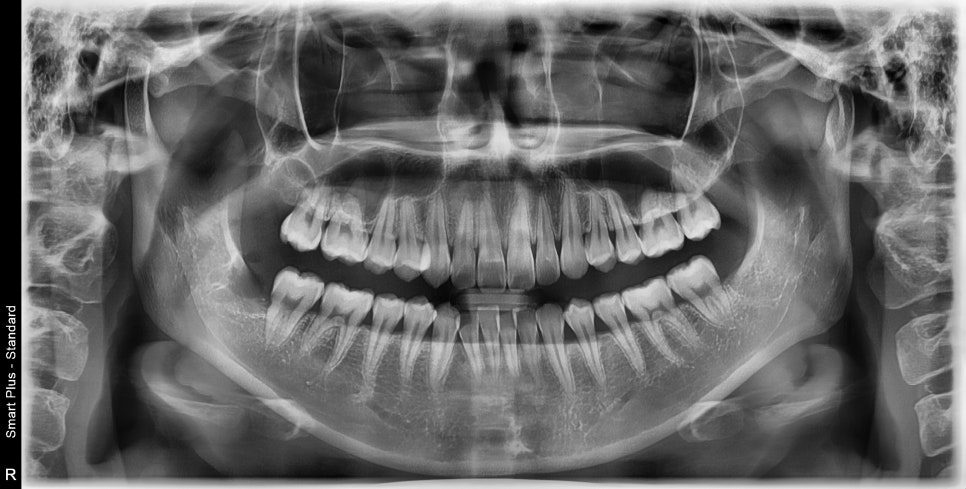

다행히 수월하게 발치 후 사진입니다.

한 환자에서 여러 가지 유형의 사랑니를 뽑아서 부위마다 붓기나 통증도 다를 것입니다.